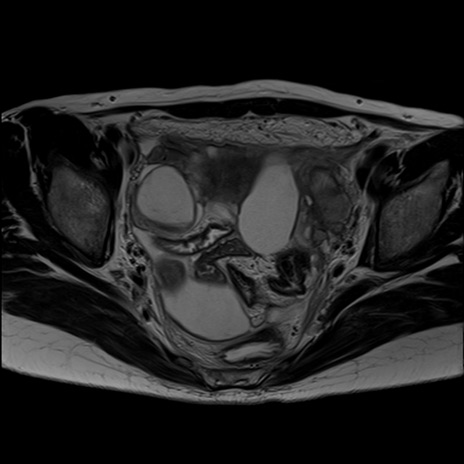

症例39 T2WI(横断像)

MRI(4日後)